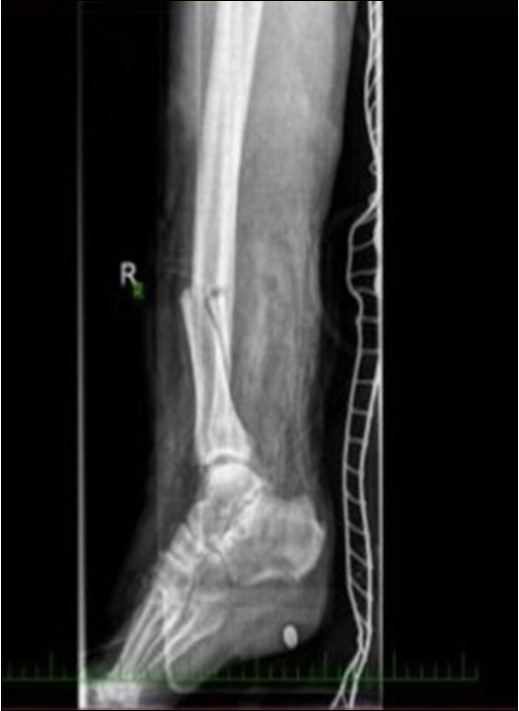

Figure 1.22 January – primary surgical treatment in the operating room

Figure 2.22 January – primary surgical treatment in the operating room

Figure 3.22 January – primary X-ray oblique splinter fracture of the tibia shaft

Figure 4.Debriteman and removal of macroscopic impurities Fracture stabilization using external fixator Reconstruction of soft tissue, subcutis and skin, necrectomy Installation of flushing lavage Covering defects with artificial skin – Syncryt

Figure 5.22 January – primary X-ray - Fracture stabilization using external fixator

Figure 6.22 January – primary X-ray - Fracture stabilization using external fixator